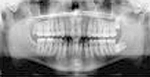

上のレントゲン写真、模型、CGのようにです。

ここで見てほしいのは歯の根っこがほぼ平行に並んでいるということです。

矯正治療というと歯の骨の外に出ている白い頭の部分を並べるモノと思われている方が多いのですが、実はそれ以上に、骨の中に埋もれている黄色い根っこの部分を並べることが大切なのです。